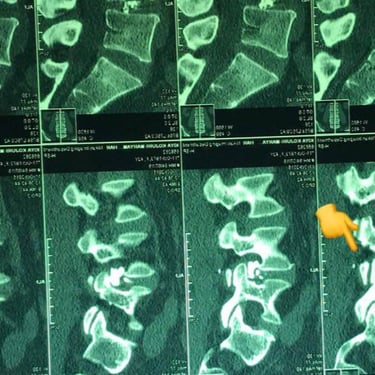

Adjacent level L1-L2 and L4-L5 disc herniations (5 years after a complicated lumbar fixation surgery) treated by Discogel Injection

Discogel in the CT Scan